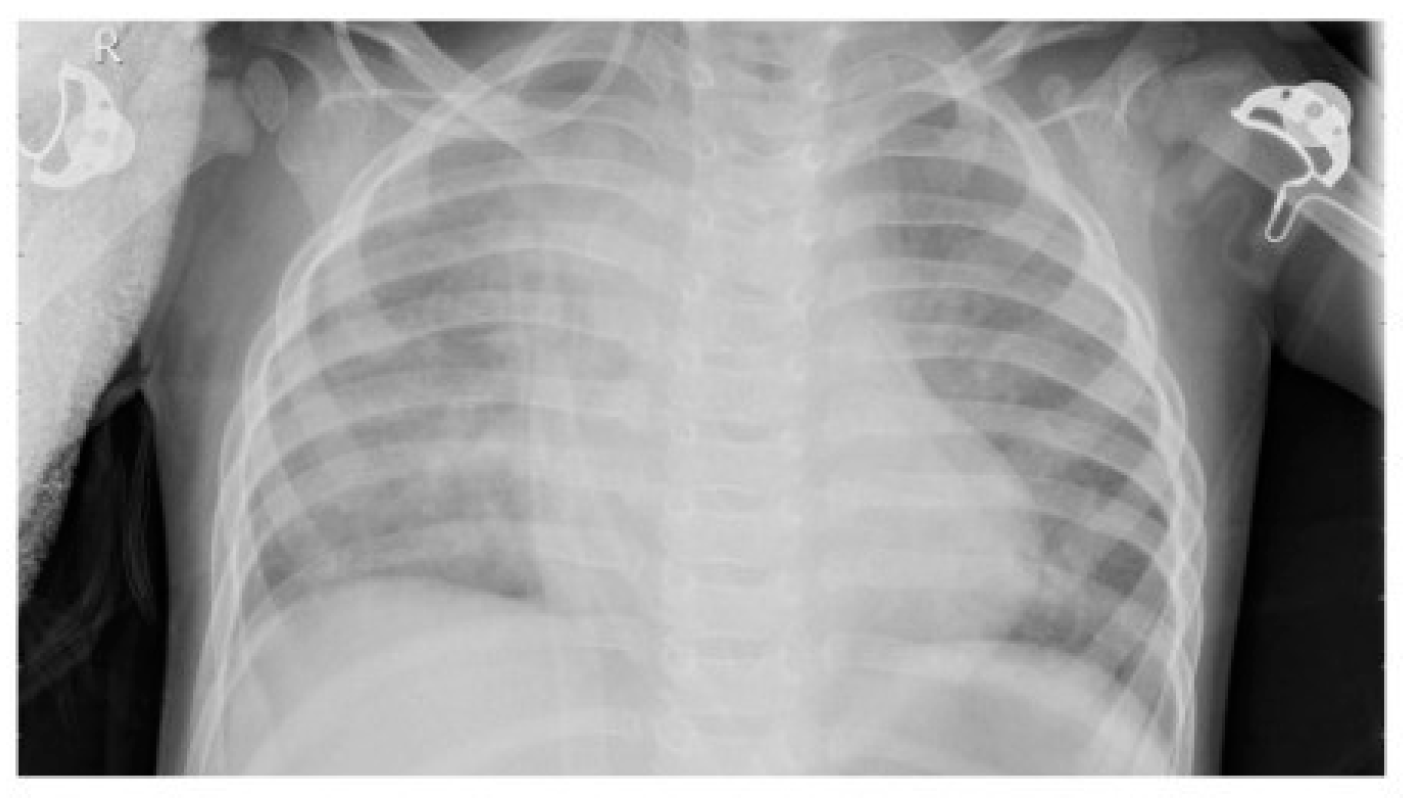

2.2. Dataset

2.4. Image Enhancement Techniques